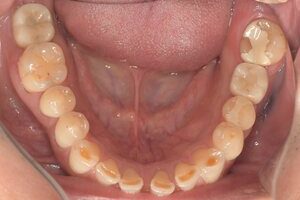

| 年齢・性別 | 40代・男性 |

|---|---|

| 主訴 | 右下7番、左下6番 |

| 治療内容 | 右下7番、左下6番のインプラント治療 |

| 治療費 | 合計:1,056,000円 【内訳】 診断料55,000円・静脈内鎮静法77,000円・ガイド66,000円・骨造成110,000円・埋入料330,000円・2次オペ44,000円・上部構造374,000円 (2024年4月現在) |

| 治療期間 | 6ヶ月 |

| リスク・副作用 | 術後は痛みや腫れ、内出血・まれに発熱する可能性があります。 術後数日は傷口より血がにじむことがあります。 一過性、場合によっては持続的に、唇・舌・頬・口蓋・歯ぐき・歯牙等の感覚麻痺・切開に起因する瘢痕組織による知覚異常が起こることがあります。 インプラントは人工物なので虫歯になることはありませんが、歯周病(インプラント周囲炎)になります。インプラントを長持ちさせるために、毎日の歯ブラシと定期検診でのクリーニングが大切です。 |

| 治療方針 | 虫歯があるため来院。左下6番は他院で抜歯済み。右下7番は虫歯が深いため当院で抜歯に。2本ともインプラント治療を選択された。 左下7番抜歯後からオペまでの間に、他の部位の虫歯治療をすすめていく。 |

| 特記事項 | インプラント体と骨の結合不全が起こる可能性があります。 その場合は治療期間が伸びることがあります。 |

| 担当者所見 | 上部構造は人工物のため欠ける可能性があります。 夜間就寝時はナイトガードを使用してもらいます。 |